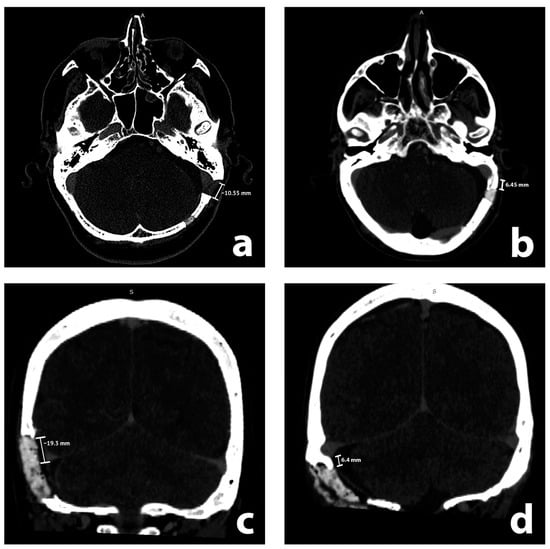

A similar analysis for the transverse sinus did not reveal such a correlation (p = 0.209, Welch’s test). A receiver operating characteristic curve analysis for the discrimination threshold for rCVST presence revealed that exposing a transverse sinus by over 6.55 mm increases the risk of rCVST (sensitivity 39%, specificity 41%, positive predictive value 37%, negative predictive value 43%, area under curve 0.367 (95% confidence interval = 0.269; 0.464), Figure 2).

Figure 2. A receiver operating characteristic (ROC) curve analysis shows that exposing a transverse sinus by over 6.55 mm increases the risk of radiologic features of cerebral venous sinus thrombosis (rCVST). ROC curve is shown in blue color, reference line is shown in grey, an optimal cut-point according to the MaxSpSe method is shown in black dashed lines.